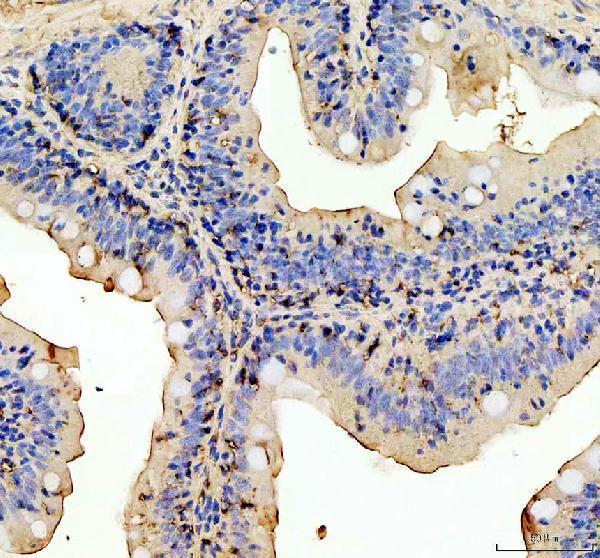

Cytoplasm. Nucleus.